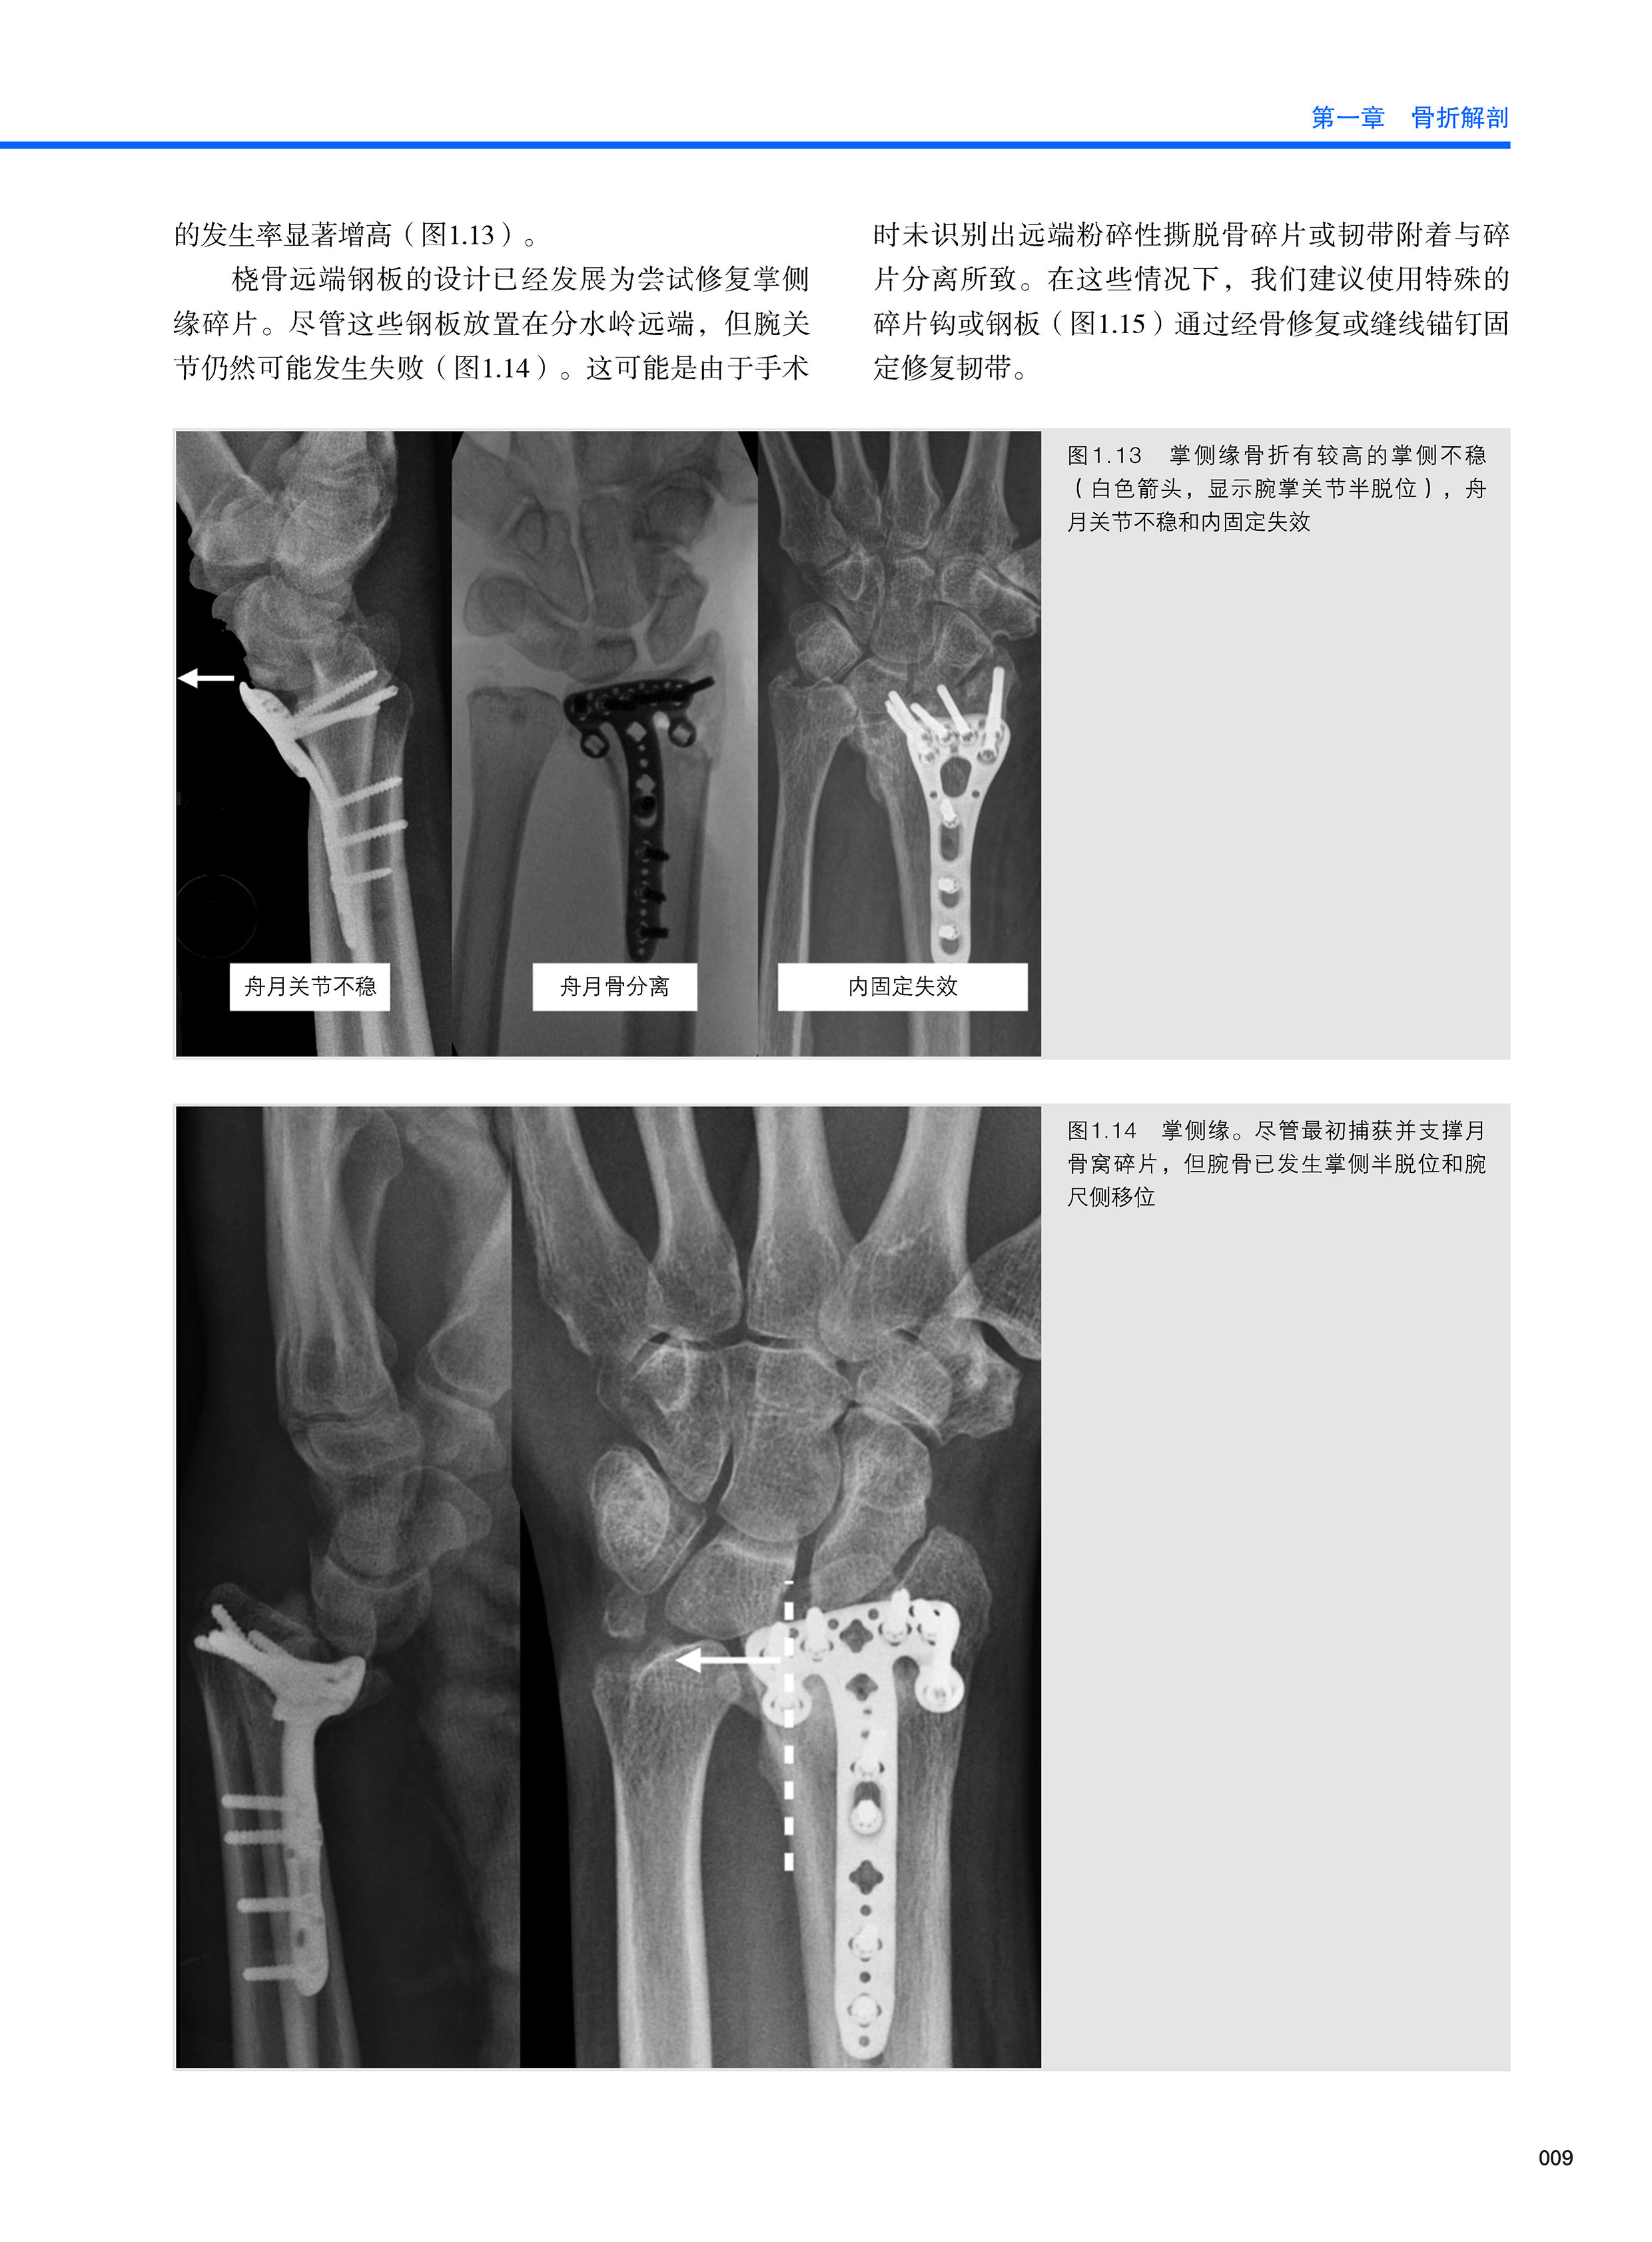

本书是关于当前热点话题—桡骨远端骨折和腕部韧带损伤的图书。 桡骨远端骨折和腕部韧带损伤的处理在过去几十年里,发生了翻天覆地的变化。 那些走在科研前沿的学者们,已经积累了诸多激动人心的经验。 从石膏、外固定架、髓内固定、掌侧或背侧板开始, 到后来的关节镜检查,所有这些都有助于为患者提供满意的治疗效果。本书汇集了当前最新的可用的技术来应对所有类型的损伤,精心挑选了一些主题,已涵盖最受关注或影响更大的主题。一些章节对一些反复出现的问题提供了新的答案或改进,希望本书可以提高患者的疗效。